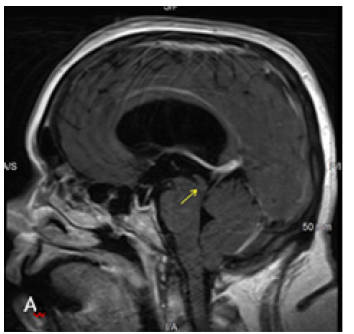

MRI brain was performed in a 3T Siemens Vireo magnet. The additional axial CISS 3D sequence was obtained with isotropic 0.6 x 0.6 x 0.6 voxels taking 7.18 minutes. Sagittal and Coronal reconstructions clearly demonstrated the AW/D Despite the Motion ArtiFact (Figure 2B) (Figure 2C).

Figure 2A:Sagittal T1 post contrast sequence with 2640 TR, 9.4 TE. Dilated lateral and third ventricles with normal appearing fourth ventricle. Aqueduct is not clearly seen in the 4mm thick slice.